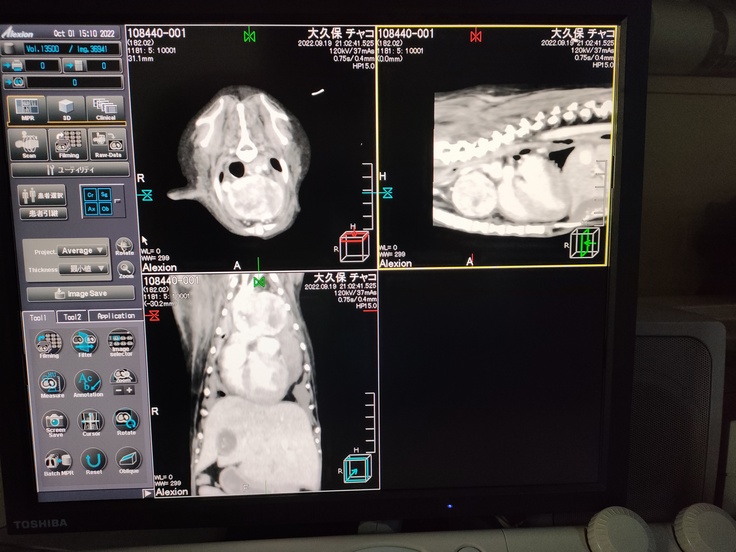

9月17日の夜中に急に元気がなくなり、歩けなくなってしまいました。その後抱きかかえようとしましたが、悲痛な叫び声をあげ、これは普通ではないと思い、救急動物病院で診察をしてもらいました。そこで、エコーをとってもらったところ、胸の心臓近くに4cm程度の腫瘍があることが判明し、その腫瘍から内出血をしていることがわかりました。病名は、「前縦隔腫瘍」です。この腫瘍から出血が発生し、胸に血液がたまり、貧血状態になっていることがわかりました。さらに、腫瘍により呼吸がしにくい状況であることも判明しました。そんな状況なので、急遽輸血などを行い、9月19日に手術をすることになりました。手術は長時間に及びましたが、開胸の結果、静脈と密接に接合しているため、腫瘍をとると失血死する可能性が高いことが判明したため、病理検査に回すための細胞をとり、手術は中断となりました。その後、順調に回復し食事も十分取れていたのですが、9月27日以降、食事をほとんどどることができず、嘔吐と下痢が続いていました。入院期間が長期になったため、かなり疲れがたまり、ストレスも溜まっているので、10月1日に急遽退院し、自宅での療養をはじめました。しかし、体調は芳しくなく、つい先日までリキッドタイプのフードでの強制給餌をしていました。ですが、10月中旬から少しずつ食事が取れるようになっており、現在は咳はでるもののある程度生活ができるようになっています。

※写真の掲載については、病院の許可をとってあります。